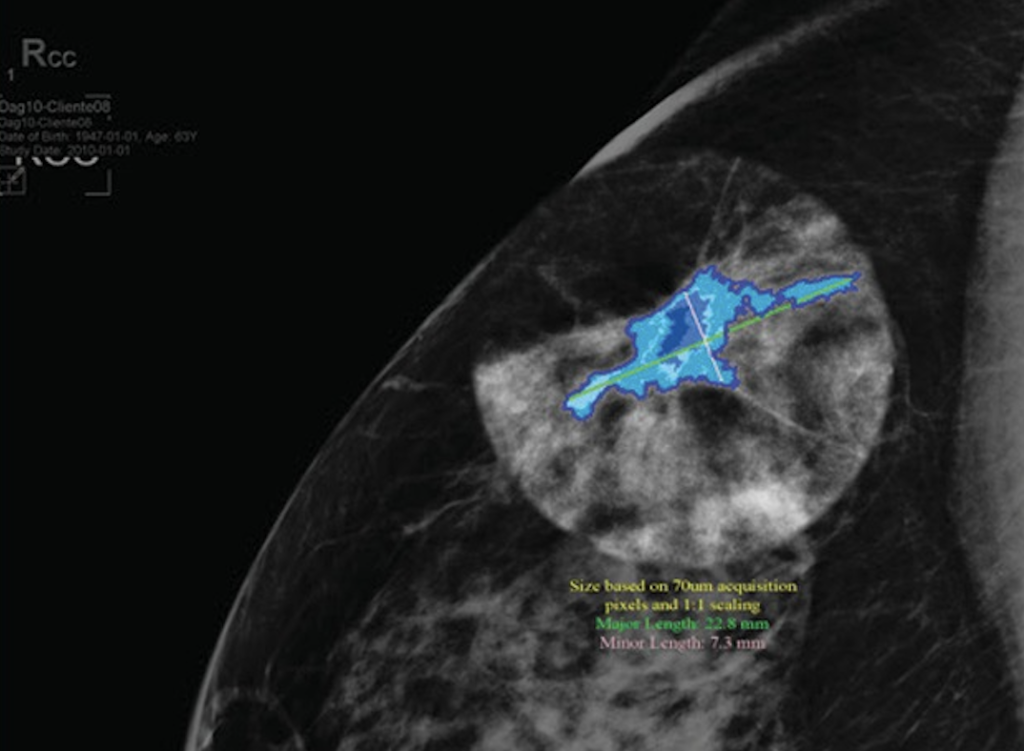

The launch of the PRECISION-DTI (Project to Review Enhanced Cancer Identification through Sensitivity and Specificity Improvements in Dense Tissue Interpretation) study was announced by DeepLook Medical, a leader in visual enhancement technology to advance medical imaging. The study will be testing its DL Precise™ imaging technology.

PRECISION-DTI will examine how DL Precise™ impacts radiologists’ accuracy, confidence and decision-making. The study will include 400 real patient cases with corresponding mammograms and ultrasound images, covering a wide range of ages, breast densities and cancer types. DL Precise™ has been approved for use in the UK and has begun commercial distribution.

Doctors participating in the study will read each case twice, first using standard imaging and then with the AI-generated measurements and overlays provided by DL Precise™. Researchers will evaluate whether the technology improves:

DL Precise™ is the first in a series of innovative products using DeepLook Medical’s unique shape-recognition software to delineate the details of tumour morphology – a key to better diagnosis and treatment across the field of oncology.